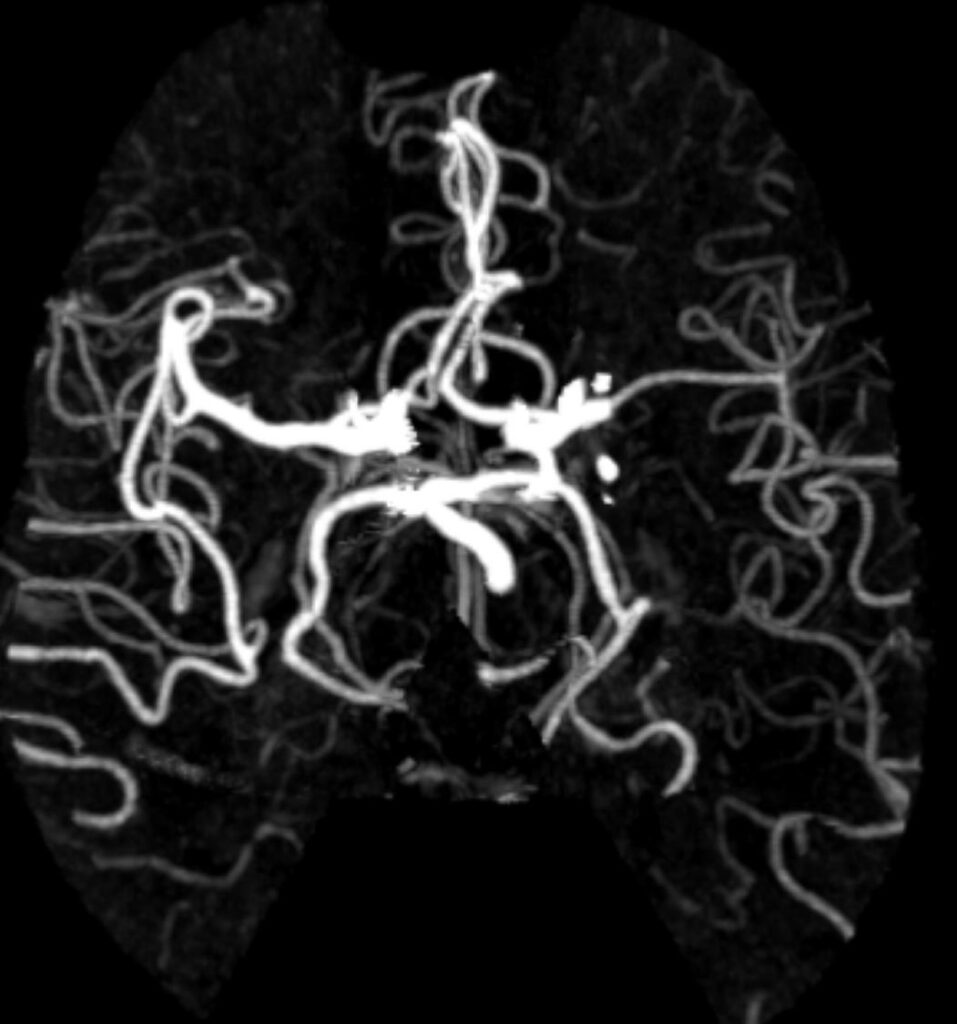

What abnormalities if any can you see?